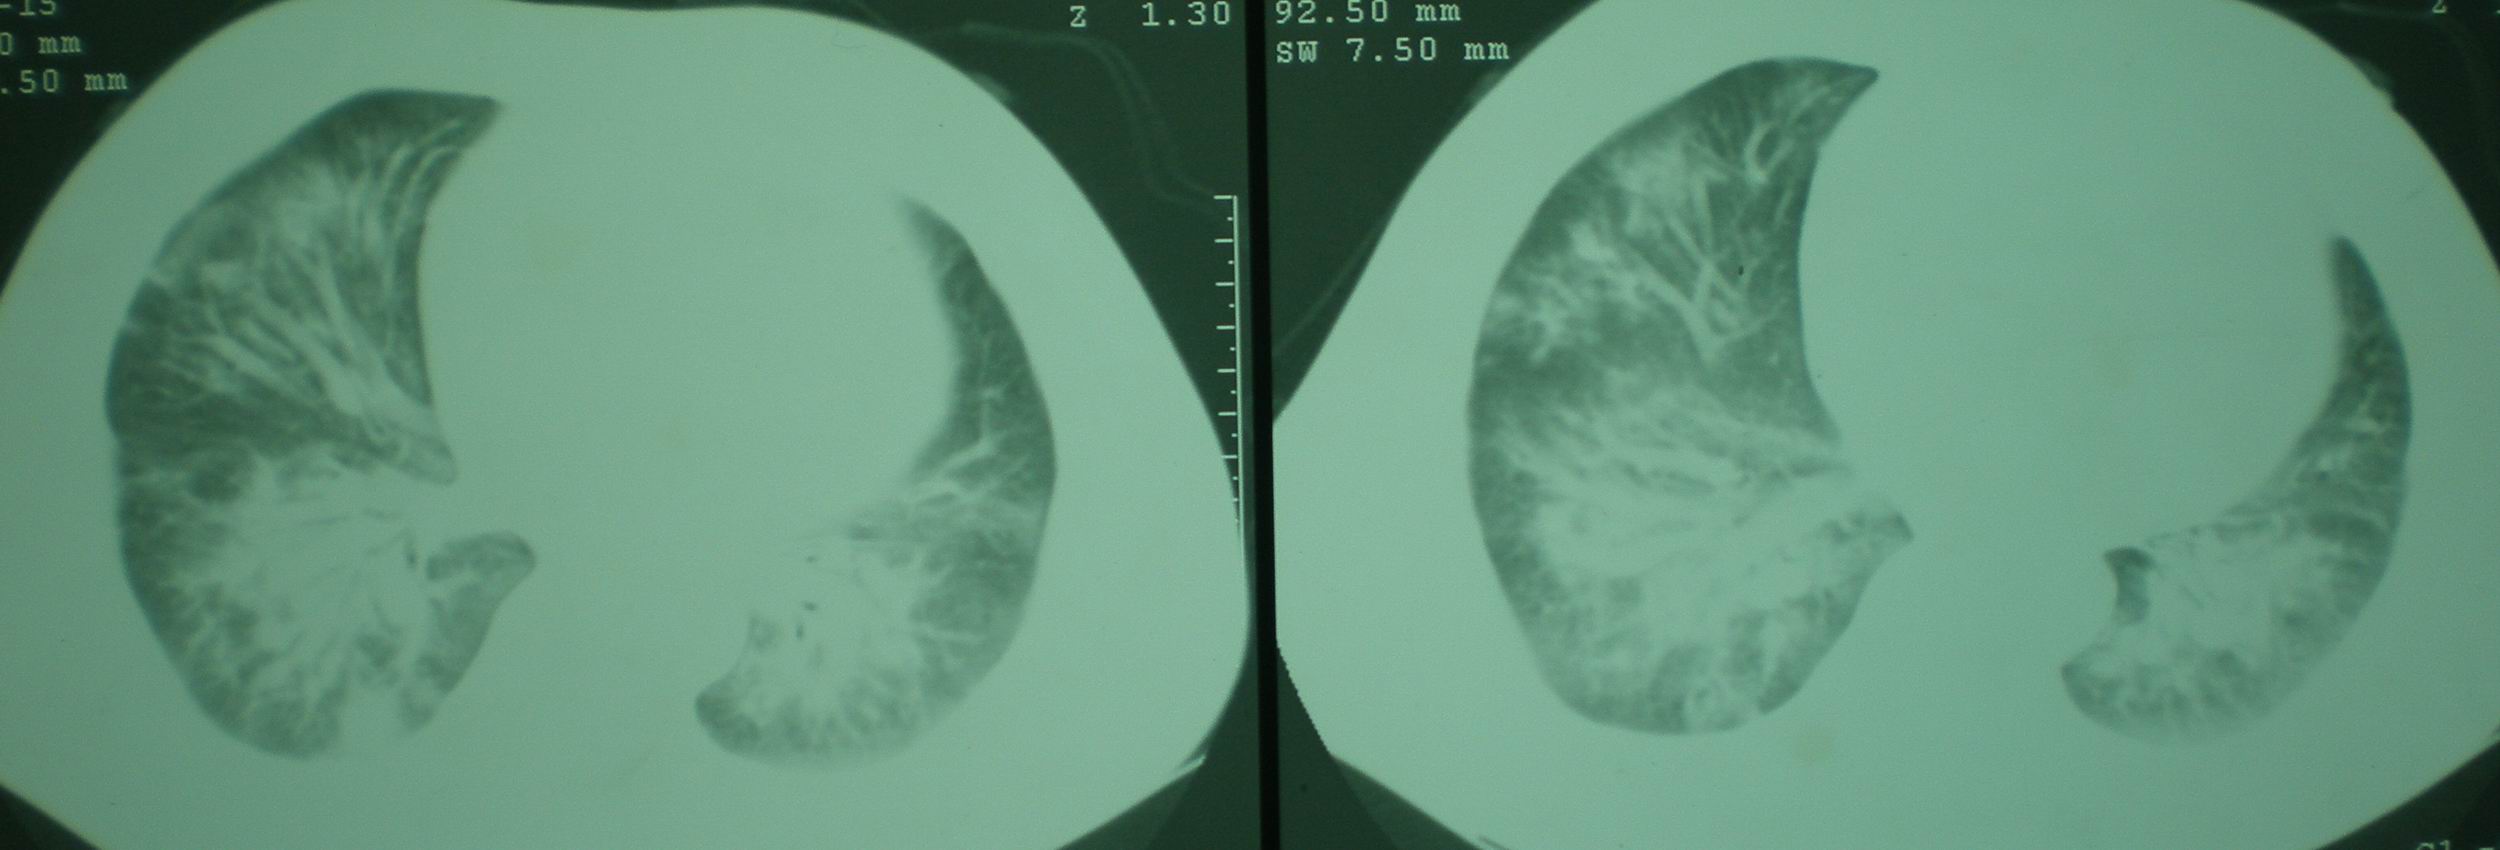

2008年11月18日今天的ct片

2008年9月18日ct片

2008年9月8日ct片:

[face=宋体]显然上级医院进行了抗结核,抗真菌,抗炎等治疗,目前病人肺内病灶基本消失,双侧胸腔积液,右侧积液量有吸收,抗结核一个多月,现在病人疑问,结核的诊断是否有疑义,抗结核是否继续,因为那个毕竟副作用大。[/face]

我仔细看了下病人的出院小结,当时情况危急,诊断里有1型呼衰。心包周围的是脂肪密度。结合三次ct扫描的图象分析,个人认为:1、病人目前肺部病灶基本消失,双侧胸腔内少量积液,抗结核治疗才一个多月,就算是结核,抗结核治疗有效果,为何效果如此好,一点纤维灶的痕迹都没有呢,再就是患者做过气管镜检查及活检、痰检均未找到结核的证据。所以不支持结核的诊断。

2、结合现在的ct片,考虑:肺水肿及真菌感染,双侧胸腔积液。

机遇性感染。双肺实质满布。且以肺门周围为主。不象结核。